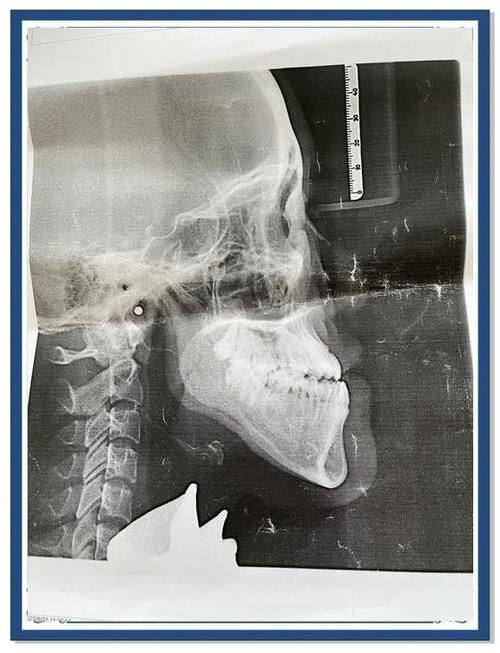

2. 口腔正畸项目:包括颌面正畸、隐形矫正等。颌面正畸可以改善患者的面部骨骼结构,解决牙齿排列不齐、咬合不良等问题,不仅能提升口腔功能,还能改善面部美观。隐形矫正则具有美观、舒适、可自行摘戴等优点,适合对美观要求较高的患者。